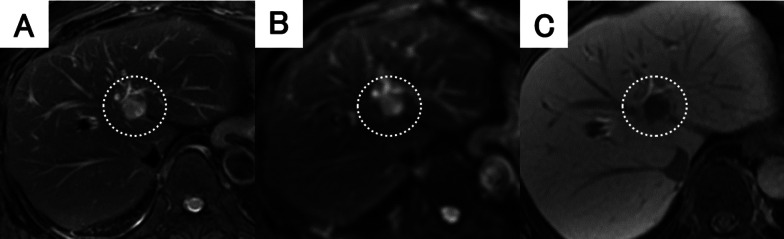

Fig. 2.

Findings of ethoxybenzyl magnetic resonance imaging (MRI). A The tumor had high signal intensity upon T2-weighted imaging. B Diffusion-weighted imaging showed high signal intensity of the tumor. C The tumor showed high intensity during the early phase and loss of primovist® uptake during the hepatocyte phase

The patient was a 66-year-old man with a history of cholelithiasis and inflammatory pseudo-tumors of the abdomen and chest wall. The patient was followed up every 6 months with MRCP and CT for the pancreatic branch type of intraductal papillary mucinous neoplasm. In 2015, computed tomography (CT) demonstrated a ~ 10 mm tumor in liver segment 4 with enhancement seen in the arterial phase (Fig. 1A, B). Based on the radiological findings, the tumor was highly suggestive of a hemangioma. As for additional testing, hepatitis B and C markers were negative, Child–Pugh grade was A, and liver damage was grade A. In addition, levels of tumor markers, such as carcinoembryonic antigen (CEA), carbohydrate antigen 19–9, and α-fetoprotein were within their respective normal ranges. The tumor gradually increased in size during the 5-year follow-up period (Fig. 1). CT revealed that the tumor size had progressed to 20 mm by 2020. The tumor showed enhancement during the arterial phase and iso-density during the late phase, which was located close to the left first branch of the Glisson (Fig. 1E, F). There was no lymph node metastasis seen around the hepatoduodenal ligament nor any distant metastases. On ethoxybenzyl magnetic resonance imaging (MRI), the tumor showed low signal intensity upon T1 weighted imaging, but high signal intensity upon T2 weighted and diffusion-weighted imaging (Fig. 2A, B). The tumor showed high intensity during the early phase and loss of primovist® uptake during the hepatocyte phase (Fig. 2C). No infiltration into surrounding vessels was observed. Positron emission tomography–CT identified an accumulation of fluorodeoxyglucose (standardized uptake value max 5.3) at the tumor site (Fig. 3). Based on these findings, the pre-operative diagnoses were HCC, ICC, and CoCC. Thereafter, left hepatectomy was performed. Intraoperatively, the liver was normal, and peritoneal seeding or ascites were not observed in the abdomen. The operative time was 424 min, and the intraoperative blood loss was 500 mL. On macroscopic examination, the tumor was well-defined, grayish-white, and solid. The tumor was 15 mm × 15 mm in diameter (Fig. 4). Microscopically, the atypical cuboidal epithelium became multi-nodular, forming small tubular glands and cord-like structures. Nuclear atypia was mild, and no mucus production was observed. Atypical, poorly formed cuboidal epithelium at the margins formed large and small dilated tubular glands, showing a cholangioma-like morphology (Fig. 5A, B). Immunohistochemical staining revealed that the cells tested positive for cytokeratin (CK)-7, CK-19, and CEA. Epithelial membrane antigen (EMA) was strongly stained in the membrane of the cancer duct, exhibiting a membranous pattern. The cytoplasm of tumor cells was positive for neural cell adhesion molecule 1 (NCAM1) (Fig. 6A, B). Based on these findings, the final pathology report revealed that the tumor was CoCC (T1N0M0, stage IA), according to the Japanese General Rules for the Clinical and Pathological Study of Primary Liver Cancer 6th edition. On the 18th post-operative day, the patient was discharged without any complications. The post-operative course of the patient was uneventful, without any recurrence happening 1 year after the surgery.